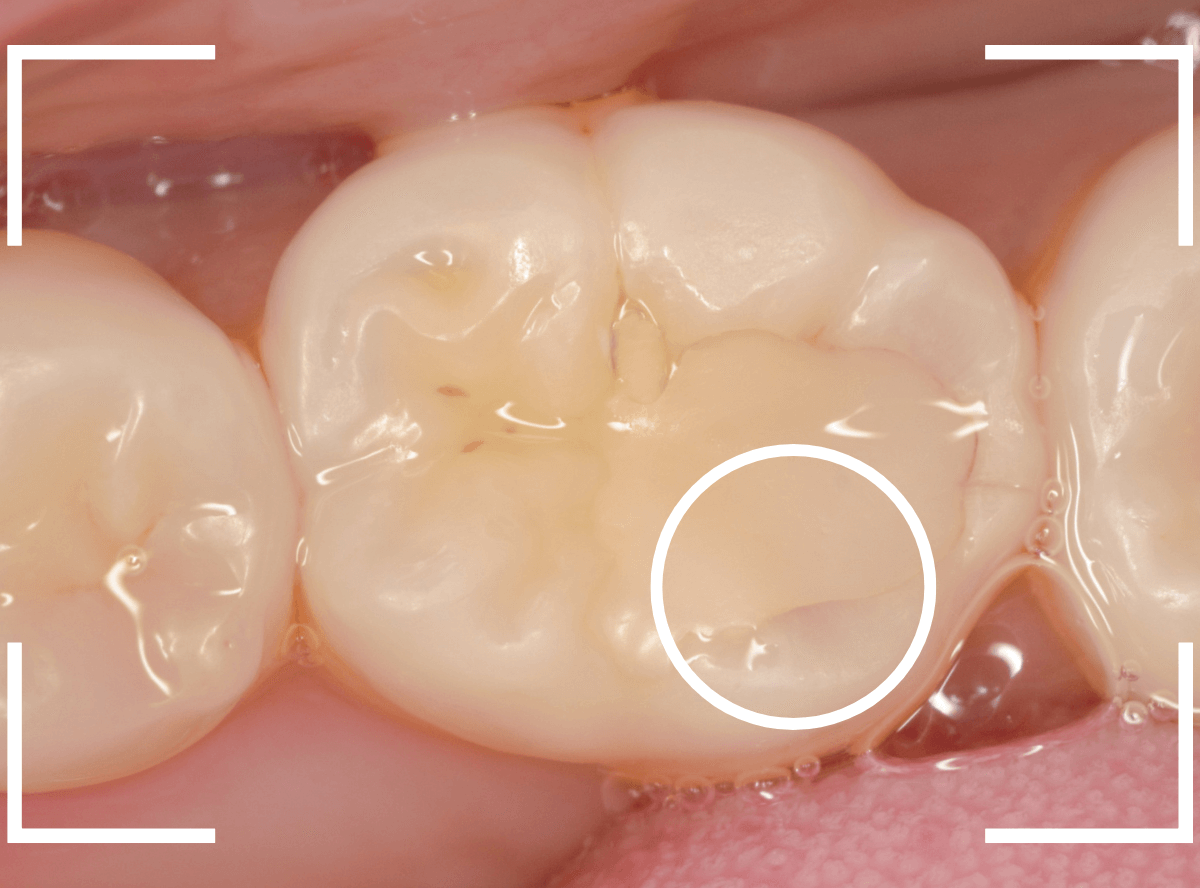

Case.17 レントゲンにはっきり写らないレジンの中の虫歯を削って調べる2

今回も、下の奥歯の虫歯を治療した例です。

特に症状はありませんが、以前に治療したレジンが劣化してすり減っているのと、少し中が黒く透けて見えて、虫歯になっているのが怪しいです。

青いラインが歯の神経です。

以前の虫歯が深めだったようで、レジンが深めにつめてあるのがわかります。

その下がうっすらと虫歯っぽい影になっています(赤いライン)。

虫歯になっているか微妙なラインですが、レジンも劣化していますので、患者さんにご説明して治療することになりました。

レントゲンで虫歯と思われる部分をレジンを除去しました。

見た目には虫歯かどうかはっきりわかりません。

う蝕検知液で染め出します。

うっすらと赤く染色されました。

レントゲン写真と同じく、レジンの下で静かに虫歯が進行し始めていたようです。

もともと深めの虫歯だった部分なので、早いうちに治療が進められてよかったです。

全てのレジンと虫歯を除去しました。

お薬をつめて、症状が出ないかしばらく経過観察します。

歯の外壁部分も薄くなってますので、レジンでは長期保存は難しいと思われます。

今回は、インレーで最終修復する予定です。